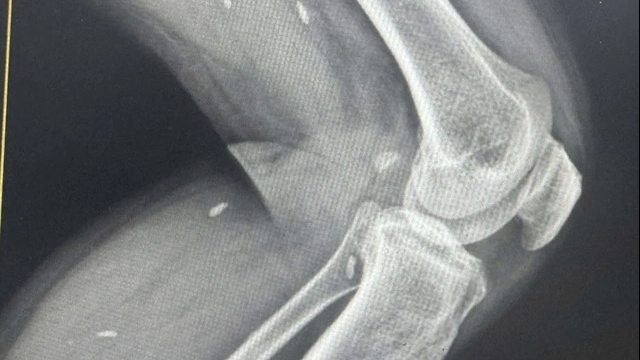

![]() |

| Sau 47 ngày điều trị liên tục, người bệnh đã hồi phục và được xuất viện. Ảnh: Bệnh viện Bạch Mai. |

Cuối tháng 12, tình trạng bệnh nhân dần ổn định, sốt được kiểm soát hoàn toàn. Ngày 6/1/2026, sau 47 ngày điều trị liên tục, người bệnh đủ điều kiện xuất viện.

Theo Bệnh viện Bạch Mai, để có được kết quả tốt, bệnh nhân và các bác sĩ đã trải qua 47 ngày giành giật sự sống, hơn 200 tờ chỉ định điều trị, gần 300 phiếu kết quả xét nghiệm, 93 cuộc hội chẩn trong đơn vị và liên chuyên khoa, 2 lần phẫu thuật.